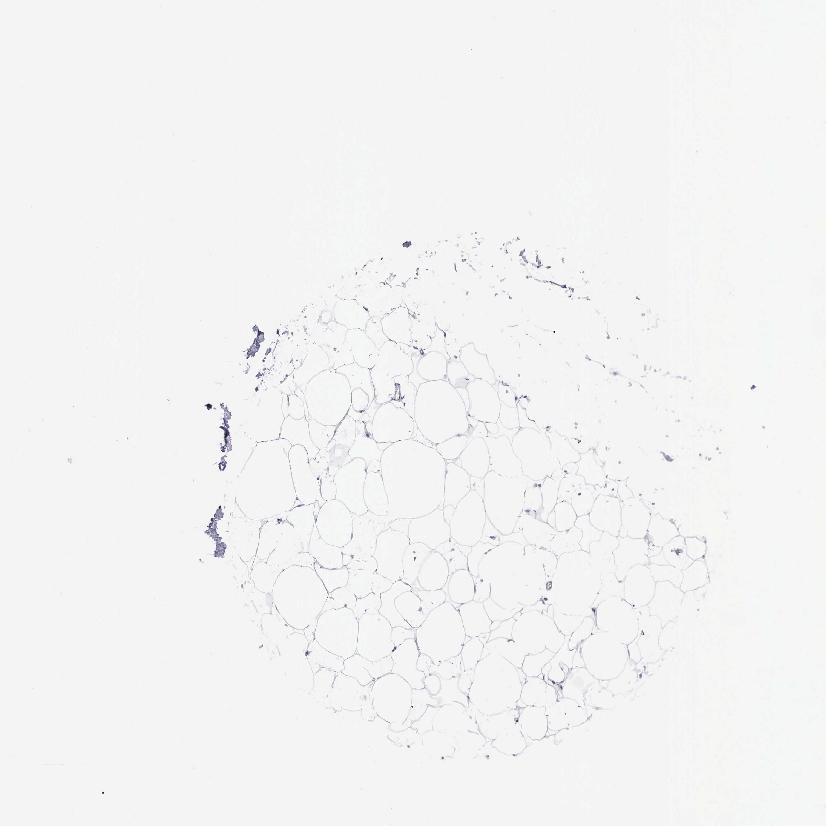

SOFT TISSUE 2 - Antibody stainingi

Antibody staining in the annotated cell types in the current human tissue is reported as not detected, low, medium, or high, based on conventional immunohistochemistry profiling in selected tissues. This score is based on the combination of the staining intensity and fraction of stained cells.

Each image is clickable and will lead to virtual microscopy that enables deeper exploration of all samples and also displays staining intensity scores, fraction scores and subcellular localization as well as patient and tissue information for each sample.

Antibody HPA003524Antibody CAB000458

Fibroblasts Not detectedNot detected

Peripheral nerve Not detectedNot detected